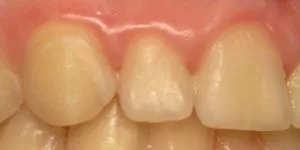

Our genetic code is responsible for the creation of our organs, including our teeth. If the genes are missing or altered somehow, the teeth made by those genes will be affected. Sometimes teeth turn out misshapen, and at times the teeth are completely missing. Our upper front side teeth are typically the ones that are affected by this congenital condition. The missing teeth often impact the smile negatively.